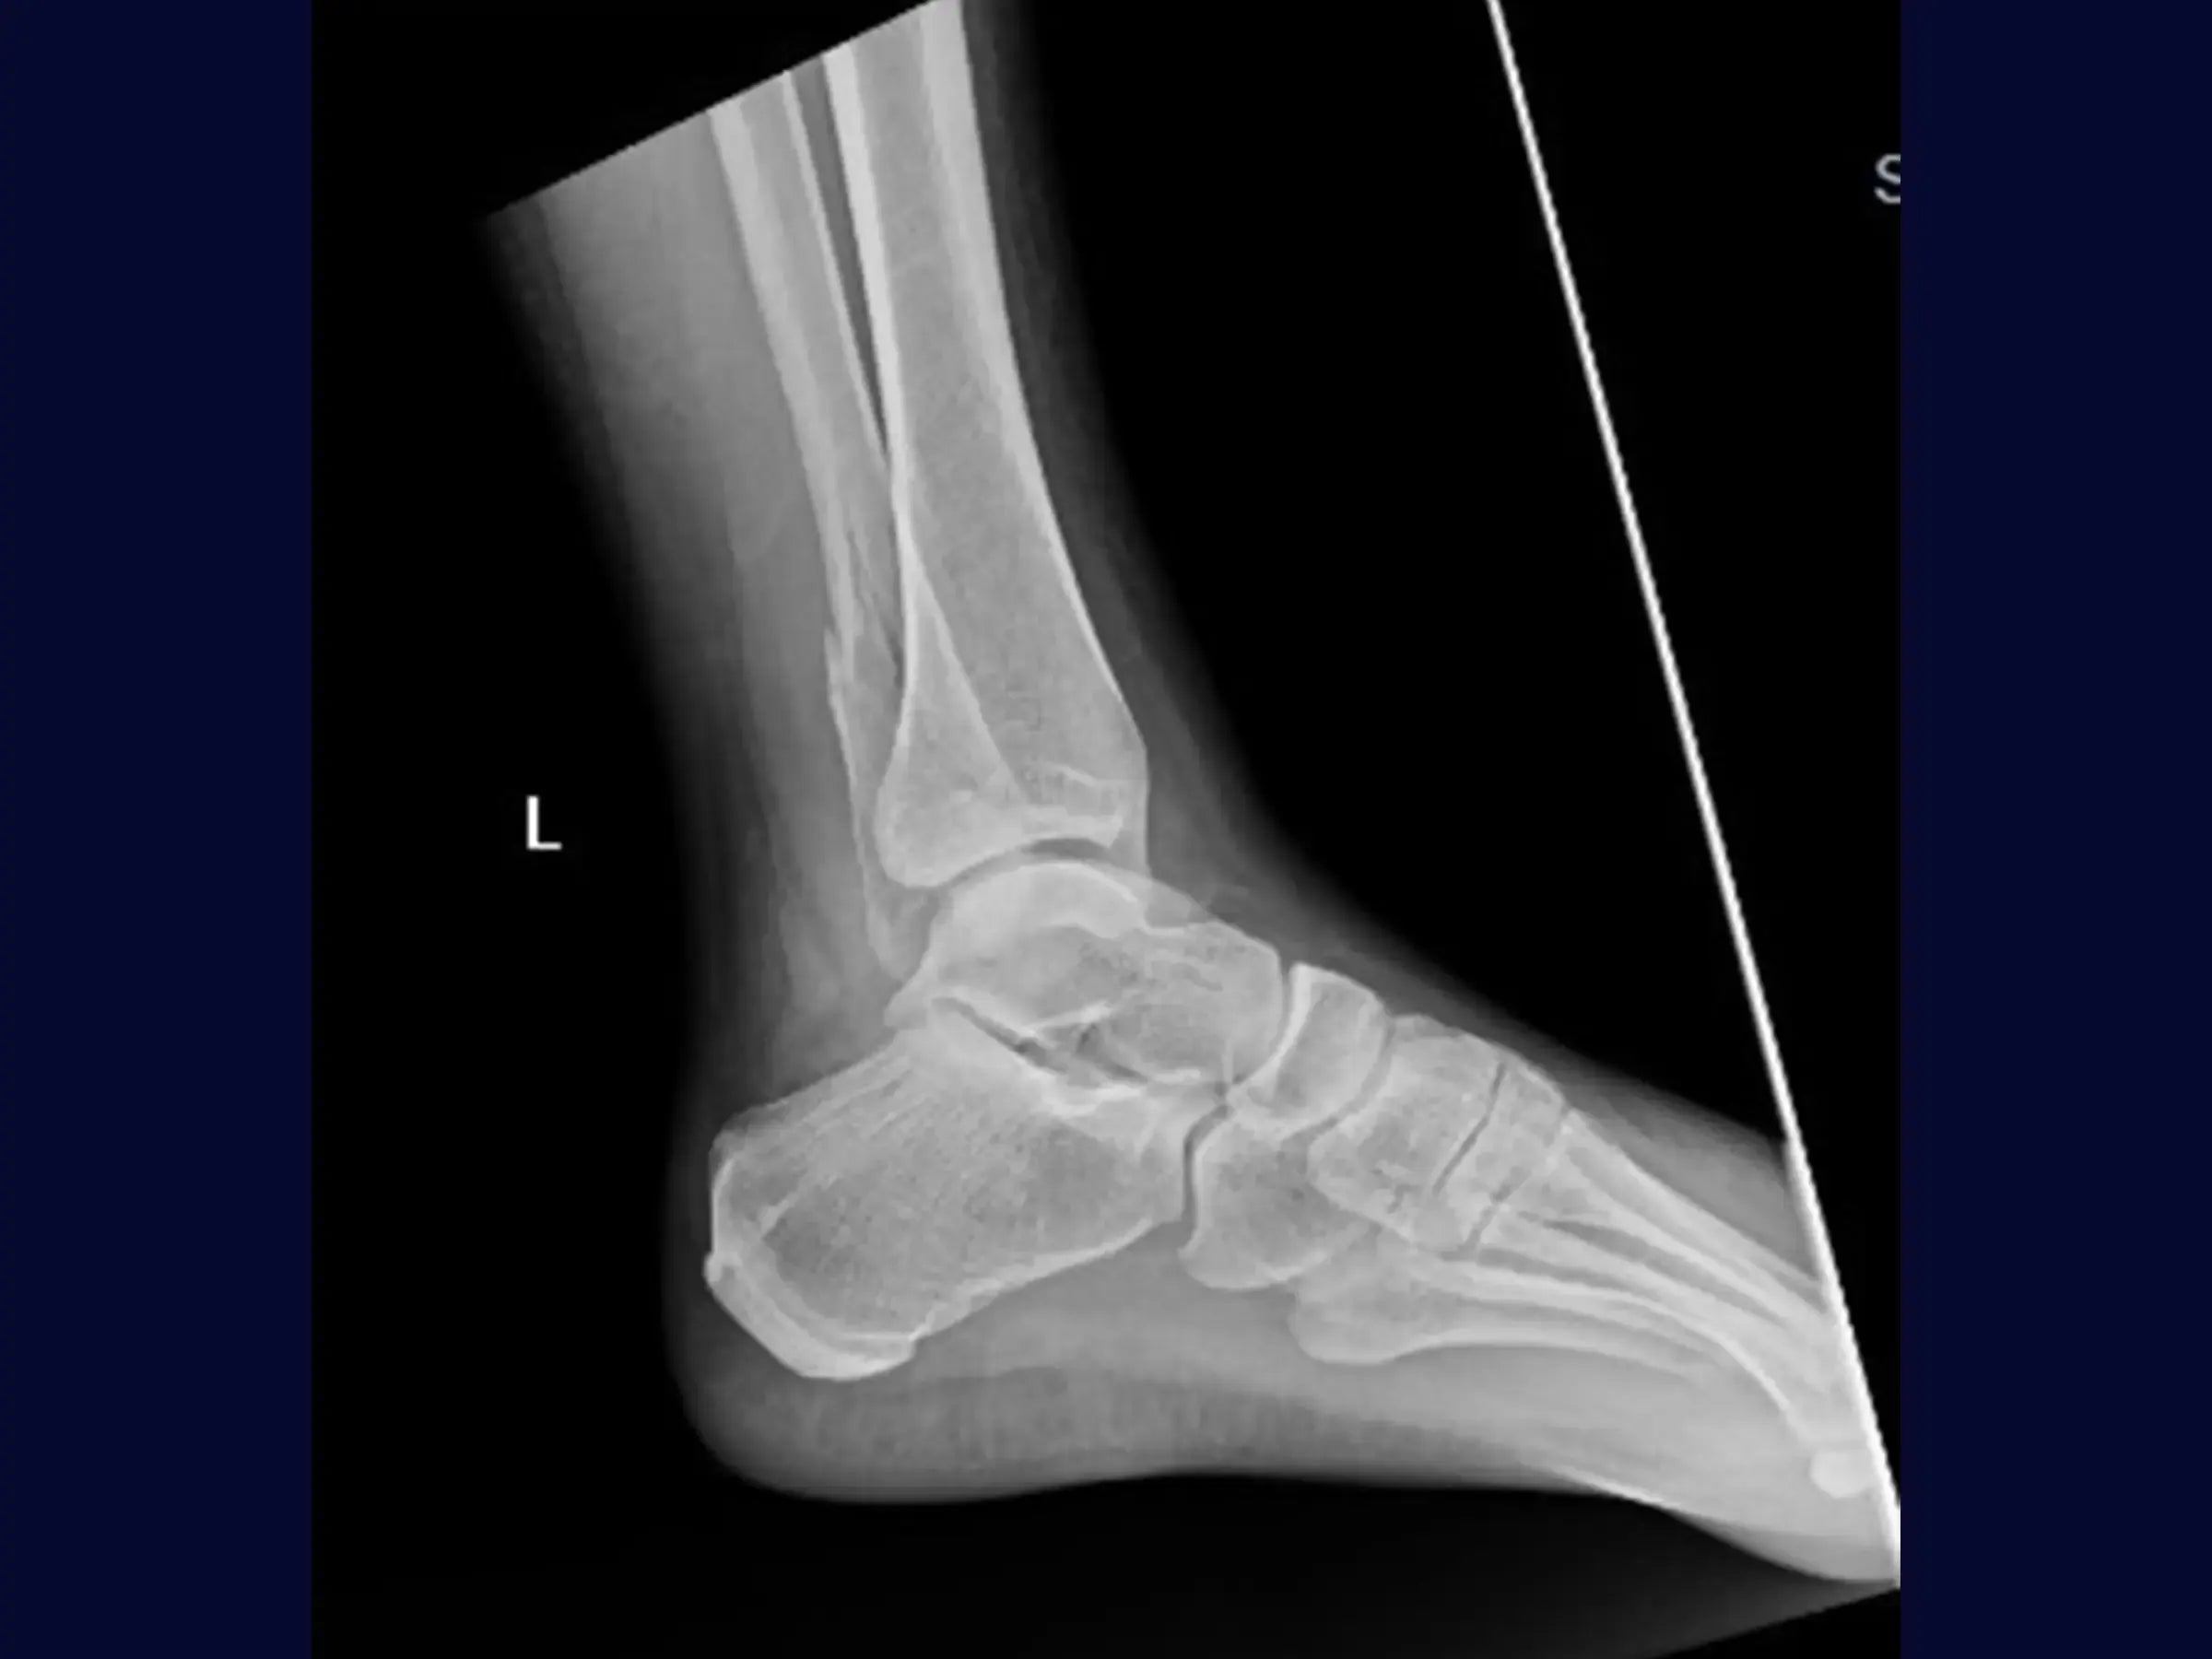

Aprimore o manejo de fraturas isoladas do maléolo lateral, especialmente as com componente multifragmentar. Este treinamento oferece uma imersão técnica na osteossíntese com placa posterior como estratégia adaptativa, apresentada em vídeo de alta resolução sob a perspectiva cirúrgica, focando na flexibilidade do planejamento intraoperatório e na mobilidade precoce.

- Tratamento cirúrgico de fraturas isoladas do maléolo lateral com componente fragmentar.

- Posicionamento Estratégico do Paciente: Otimização do campo cirúrgico e facilitação do acesso para o cirurgião.

- Acesso Cirúrgico Lateral Formal: Garantia de campo limpo e identificação precisa da fratura.

- Redução Anatômica por "Dentes da Fratura": Técnica para identificar e coaptar os fragmentos com precisão.